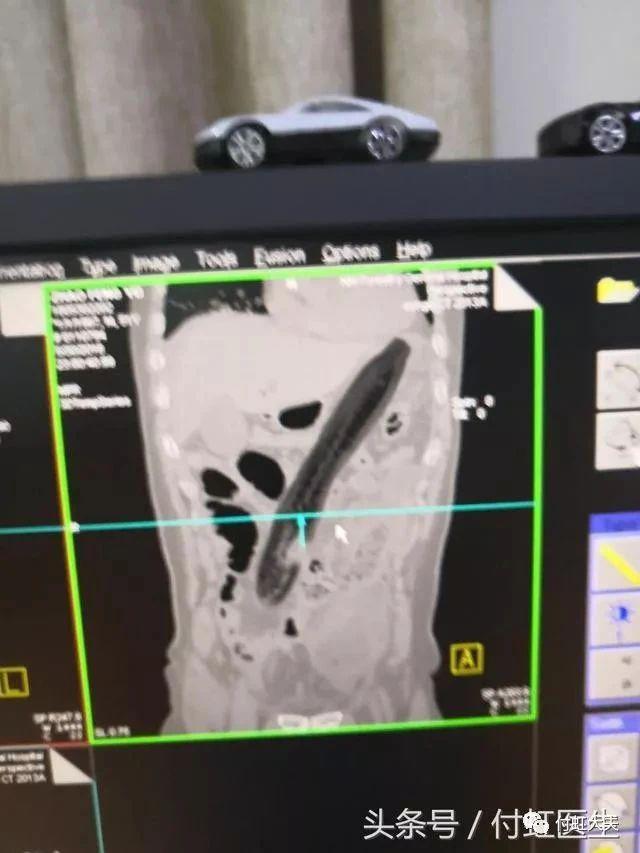

40 多岁男子,因为听信网上治疗前列腺增生的偏方,把三条大泥鳅塞进肛门。

罗非鱼直肠,罗非鱼塞进直肠多长时间